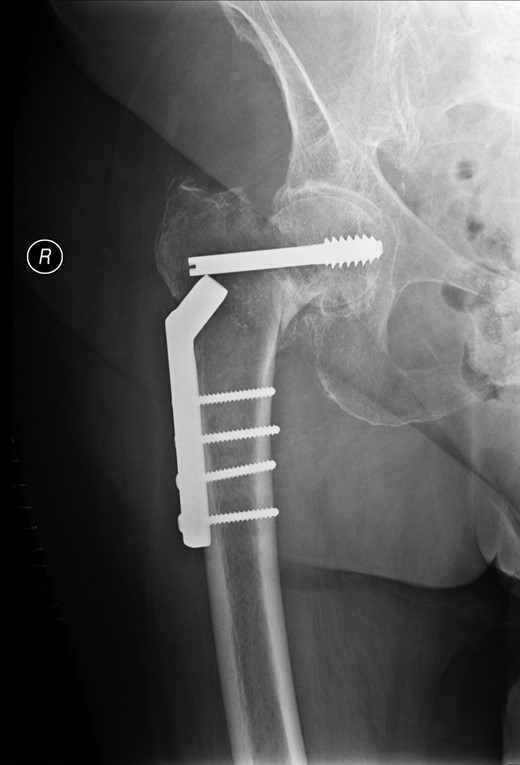

Post-operative nausea delayed immediate attempts at rehabilitation. Although she sat out in a chair, transfers were accomplished with a hoist. At 10 days, post-operatively she was transferred to a peripheral hospital, where rehabilitation commenced with a 2-min period of standing with support. The following morning she complained of greatly increased pain in the operated hip. A radiograph showed that the screw had separated from the barrel, as shown in Fig. 3.